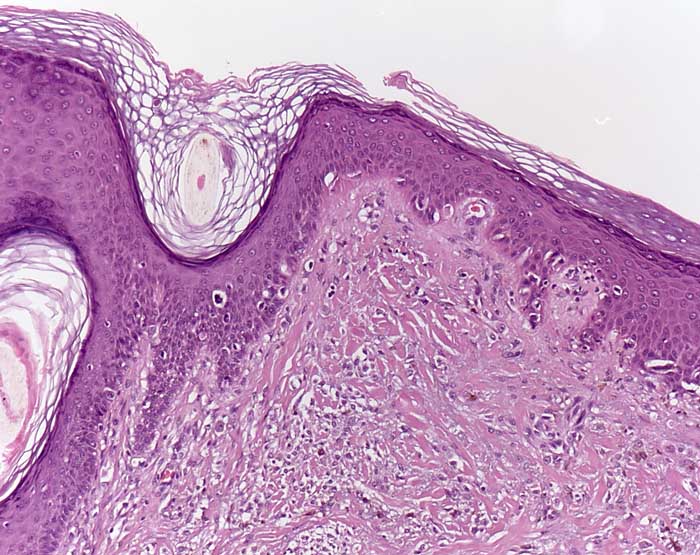

PathoPic – image database / PathoPic ID 7757 - Desmoplastisches Melanom (Lentigo maligna Melanom)

Desmoplastisches Melanom (Lentigo maligna Melanom)

Lentiginöse Hyperplasie atypischer Melanozyten entlang der Junktionszone entsprechend einer Lentigo maligna. Die angrenzende Dermis ist narbenartig fibrosiert und ist auffallend zellreich (desmoplastisches Melanom). Die dermalen Zellen weisen lediglich geringe Atypien auf.

Histologie

Vergrösserung